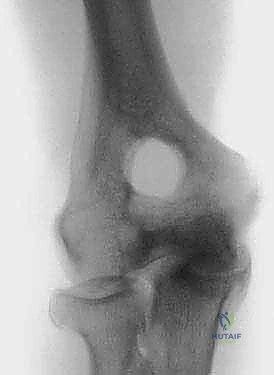

- الأشعة السينية (X-rays): الفحص الأساسي لرؤية العظام. تُظهر الأشعة السينية بوضوح تضيق المسافة المفصلية، وجود النتوءات العظمية (المهماز العظمي) في الحفرة الزجية والإكليلية، والأجسام الحرة الكبيرة.

- الأشعة المقطعية ثلاثية الأبعاد (3D CT Scan): تُعد الأداة الأهم للتخطيط الجراحي لعملية أوتبيردج-كاشيواجي. توفر خريطة دقيقة ثلاثية الأبعاد لحجم وموقع النتوءات العظمية، وتساعد الدكتور هطيف على تحديد كمية العظام التي يجب إزالتها بدقة مليمترية.

هذه النتوءات هي السبب الرئيسي للألم وتحديد الحركة؛ حيث تصطدم ببعضها البعض (Impingement) أو تحتك بالعظام المقابلة عند محاولة تحريك الكوع. كما يمكن أن تنفصل أجزاء صغيرة من هذه النتوءات أو الغضاريف المتآكلة لتتكون "أجسام حرة" (Loose Bodies) تسبح داخل السائل المفصلي، وهي قطع صغيرة يمكن أن تنحشر بين أسطح المفصل مسببة ألماً مفاجئاً حاداً، طقطقة مسموعة، أو قفلاً كاملاً للمفصل (Joint Locking).

يتكون الجزء البعيد من عظم العضد من لُقمتين: البكرة الإنسية (Medial Trochlea) والرؤيس الوحشي (Lateral Capitellum). فوق هذه الأسطح المفصلية مباشرة، توجد تجاويف هامة جداً:

في حالات خشونة الكوع، تمتلئ هذه الحفر بالنتوءات العظمية والأنسجة الليفية، مما يمنع العظام من الدخول في أماكنها الطبيعية، وهذا هو التفسير الميكانيكي لعدم قدرة المريض على فرد أو ثني ذراعه بالكامل.

- العصب الزندي (Ulnar Nerve): يُعد هذا العصب أهم ما يثير قلقنا في أي جراحة للكوع. يمر العصب الزندي خلف النتوء الداخلي للكوع (Medial Epicondyle) في نفق ضيق يُعرف بالنفق المرفقي (Cubital Tunnel). في كثير من حالات خشونة الكوع، تضغط النتوءات العظمية على هذا العصب، مما يسبب خدراً وتنويلاً في الإصبع الصغير ونصف الإصبع البنصر، وضعفاً في قبضة اليد.